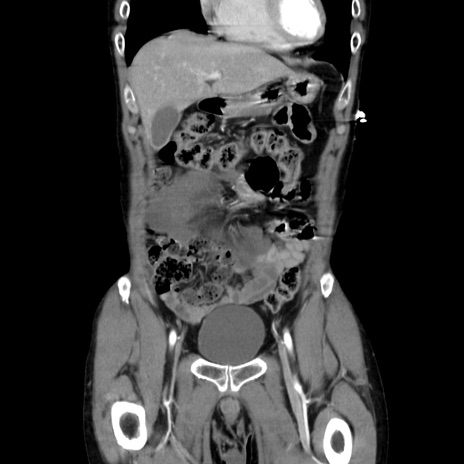

症例37(冠状断像)

【症例】40歳代 男性

【主訴】腹痛

【現病歴】4時間ほど前に電車に乗車中に臍部上より腹痛出現。徐々に増悪し起立困難となり、救急外来受診。生ものは数日食べていない。今朝お雑煮を食べた。

【身体所見】BT 36.8℃、BP 117/84mmHg、HR 91/min、SpO2 97%、苦悶様、腹部:臍上部広範囲圧痛あり、反跳痛±

【データ】WBC 8100、CRP 0.03